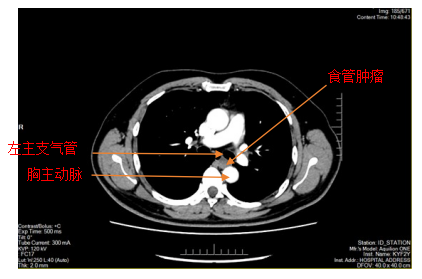

胸部增强CT

患者李某因胸骨后异物感20余天入院,在外院进行胃镜检查提示食管距门齿约26cm处见黏膜下肿瘤,在亚洲色吧 附二院超声胃镜提示该肿瘤呈低回声,局限于黏膜下层,固有肌层完整;胸部CT提示该肿瘤直径>2cm,位于食管中下段,增强扫描轻度强化,前与左主支气管相邻,后紧贴胸主动脉,手术过程中稍有不慎就可能发生大出血,危及患者生命,手术难度和风险可想而知。